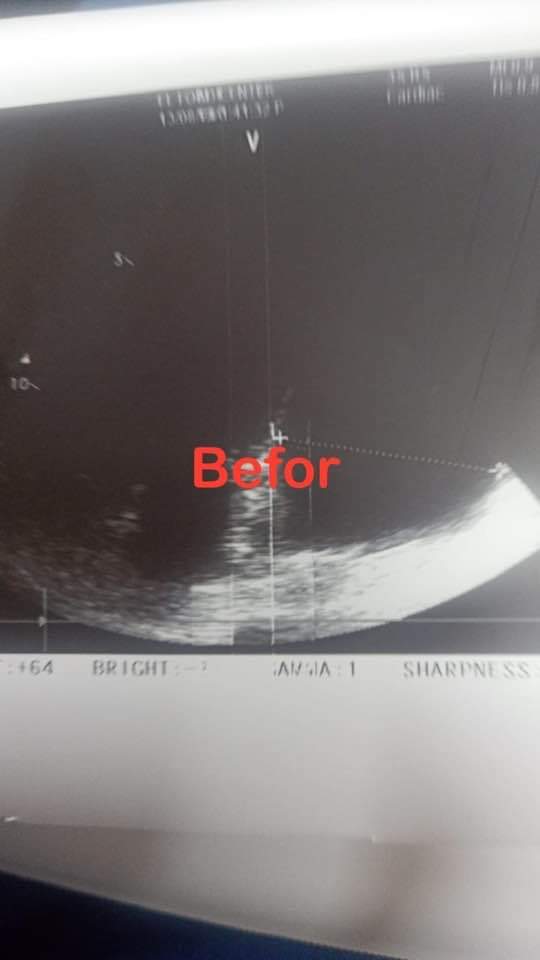

وتابع الدكتور حلمي عبد الرحمن: بمراجعة الحالة الإكلينيكية للمريضة وعمل الموجات الصوتية للقلب تبين عدم صحة التشخيص مع تجمع للسوائل حول عضلة القلب بكميات كبيرة جعلت القلب كأنه يسبح في بركة من السوائل الأمر الذي أدى إلى تأثر العلامات الحيوية وعدم قدرة القلب على القيام بمهامه.

وأوضح أنه تم تحضير المريضة للدخول للعمليات وفي وقت قياسي وبدون انتظار أي إجراءات تم دخولها العمليات وسحب ما يقرب من لتر من السائل حول عضلة القلب حتى عادت المريضة وعلاماتها الحيوية لمعدلاتها الطبيعية.